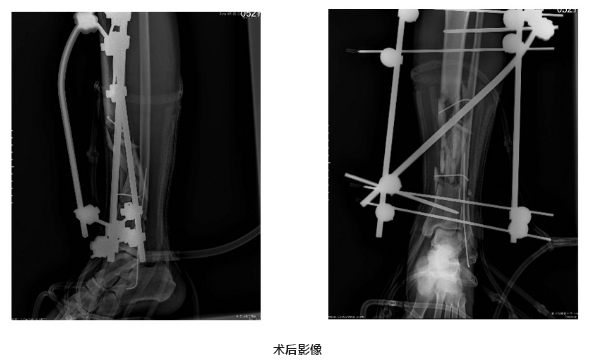

冯子明有丰富的四肢毁损伤保肢经验,患者到达医院后,在各专科的配合下立即进行手术,对接断裂血管、复位固定骨折、修复断裂肌肉,术后下肢恢复血运良好。经过骨科一区医护人员悉心照顾治疗,术后三十天创面基本愈合,肢体血运良好,保肢成功。黄先生及家属对冯子明医师团队感恩不已,黄先生一再表示,这次能保肢成功十分感谢医院。

患者伤处影像